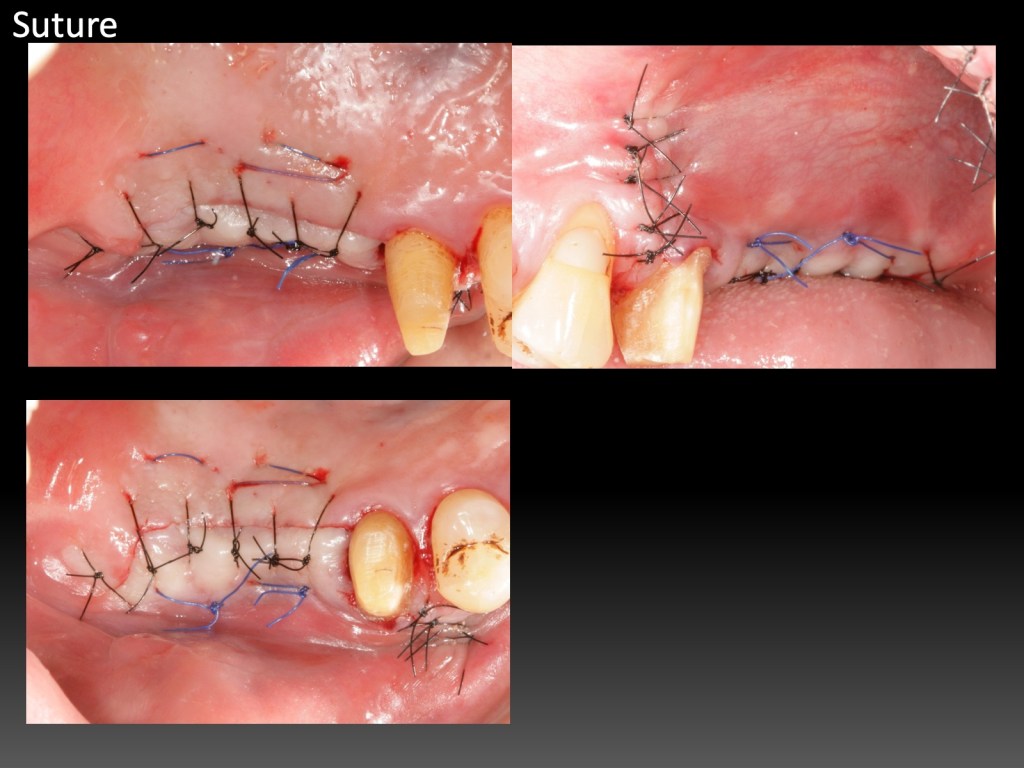

Increase Keratinized Tissue of Lingual Aspect 增加舌側角化組織

GBR的舌側提升,會讓內側角化組織變少,或是,案例即使沒補骨,原本就舌側角化組織缺乏。這幾年自己也想解決這個難題。試了幾個不同做法,有一些心得。

一開始的Partial Thickness皮瓣移動,只須刀片劃開表層,其餘用鈍器械推下去。跟Tension free flap release這篇的手法類似。意即,切得少,推得多。

固定的關鍵,這幾年我發現,是縫針。因為有舌頭會移動,空間小,不易操作,而且進針、取針時機很短。縫針找1/2彎度,短如10mm,短進短出,要快,沒有多餘時間再找針頭。針還要利,故角針遠比圓針更好。個人經驗,縫針規格,3/8 彎度,13mm以上,也可以,但是會增加手術難度。短、勾、銳,很重要。

還有另一個固定的技巧。一開始graft容易滑動,用針進出graft,不容易固定。不如專注在cross mattress進出旁邊的骨膜上,利用縫線先將graft壓住。縫到尾聲再用針進出graft,做最後固定。

2024/5/26 更新:新增七個月追蹤,特寫MGJ真實位置